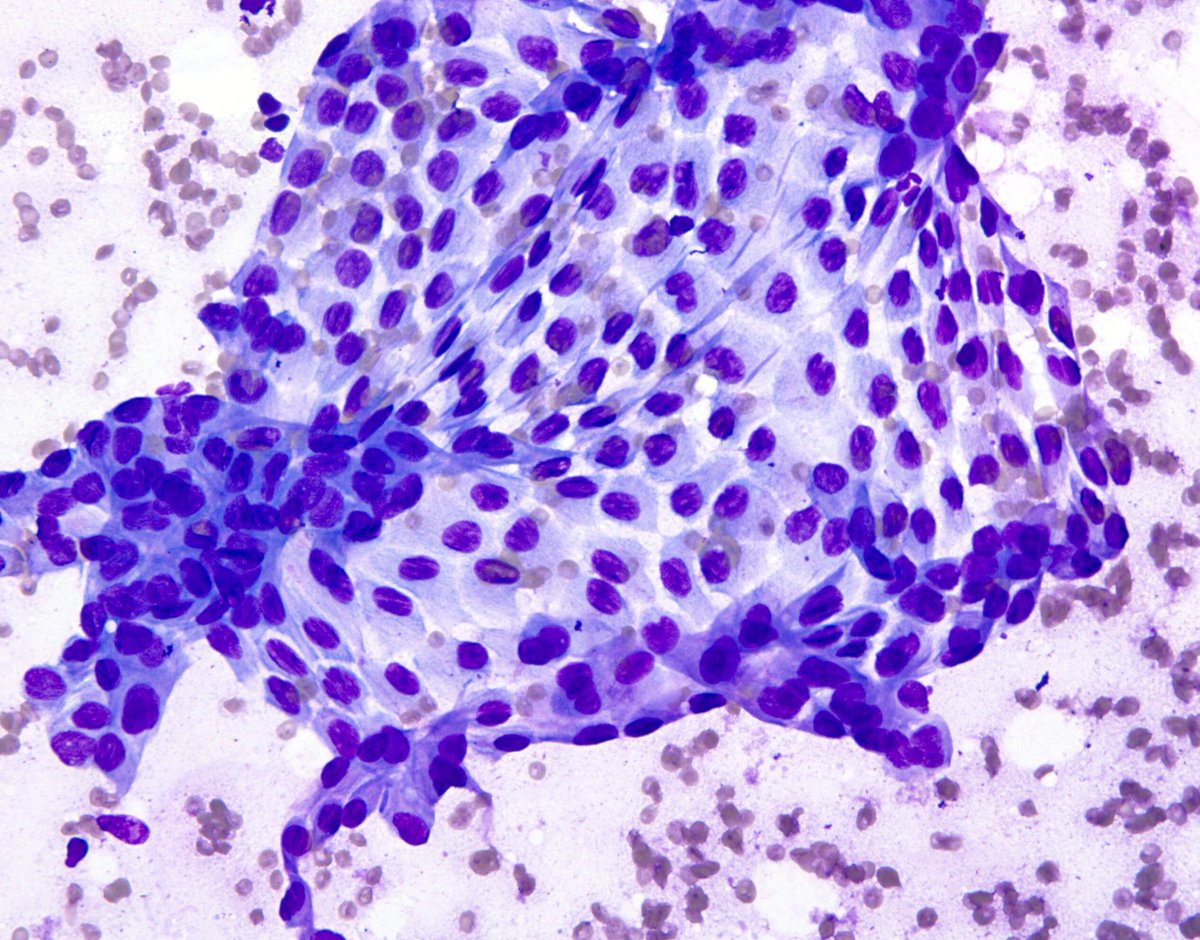

"Two-in-one": lung AC in a pleural effusion: the same cells stained with papanicolaou and then with TTF1. "Cytopathology, doing more with less...."🔬✌️🎯💯🔝 Sociedad Española de Citología SEAP-IAP Cytopathology.org International Academy Cytology